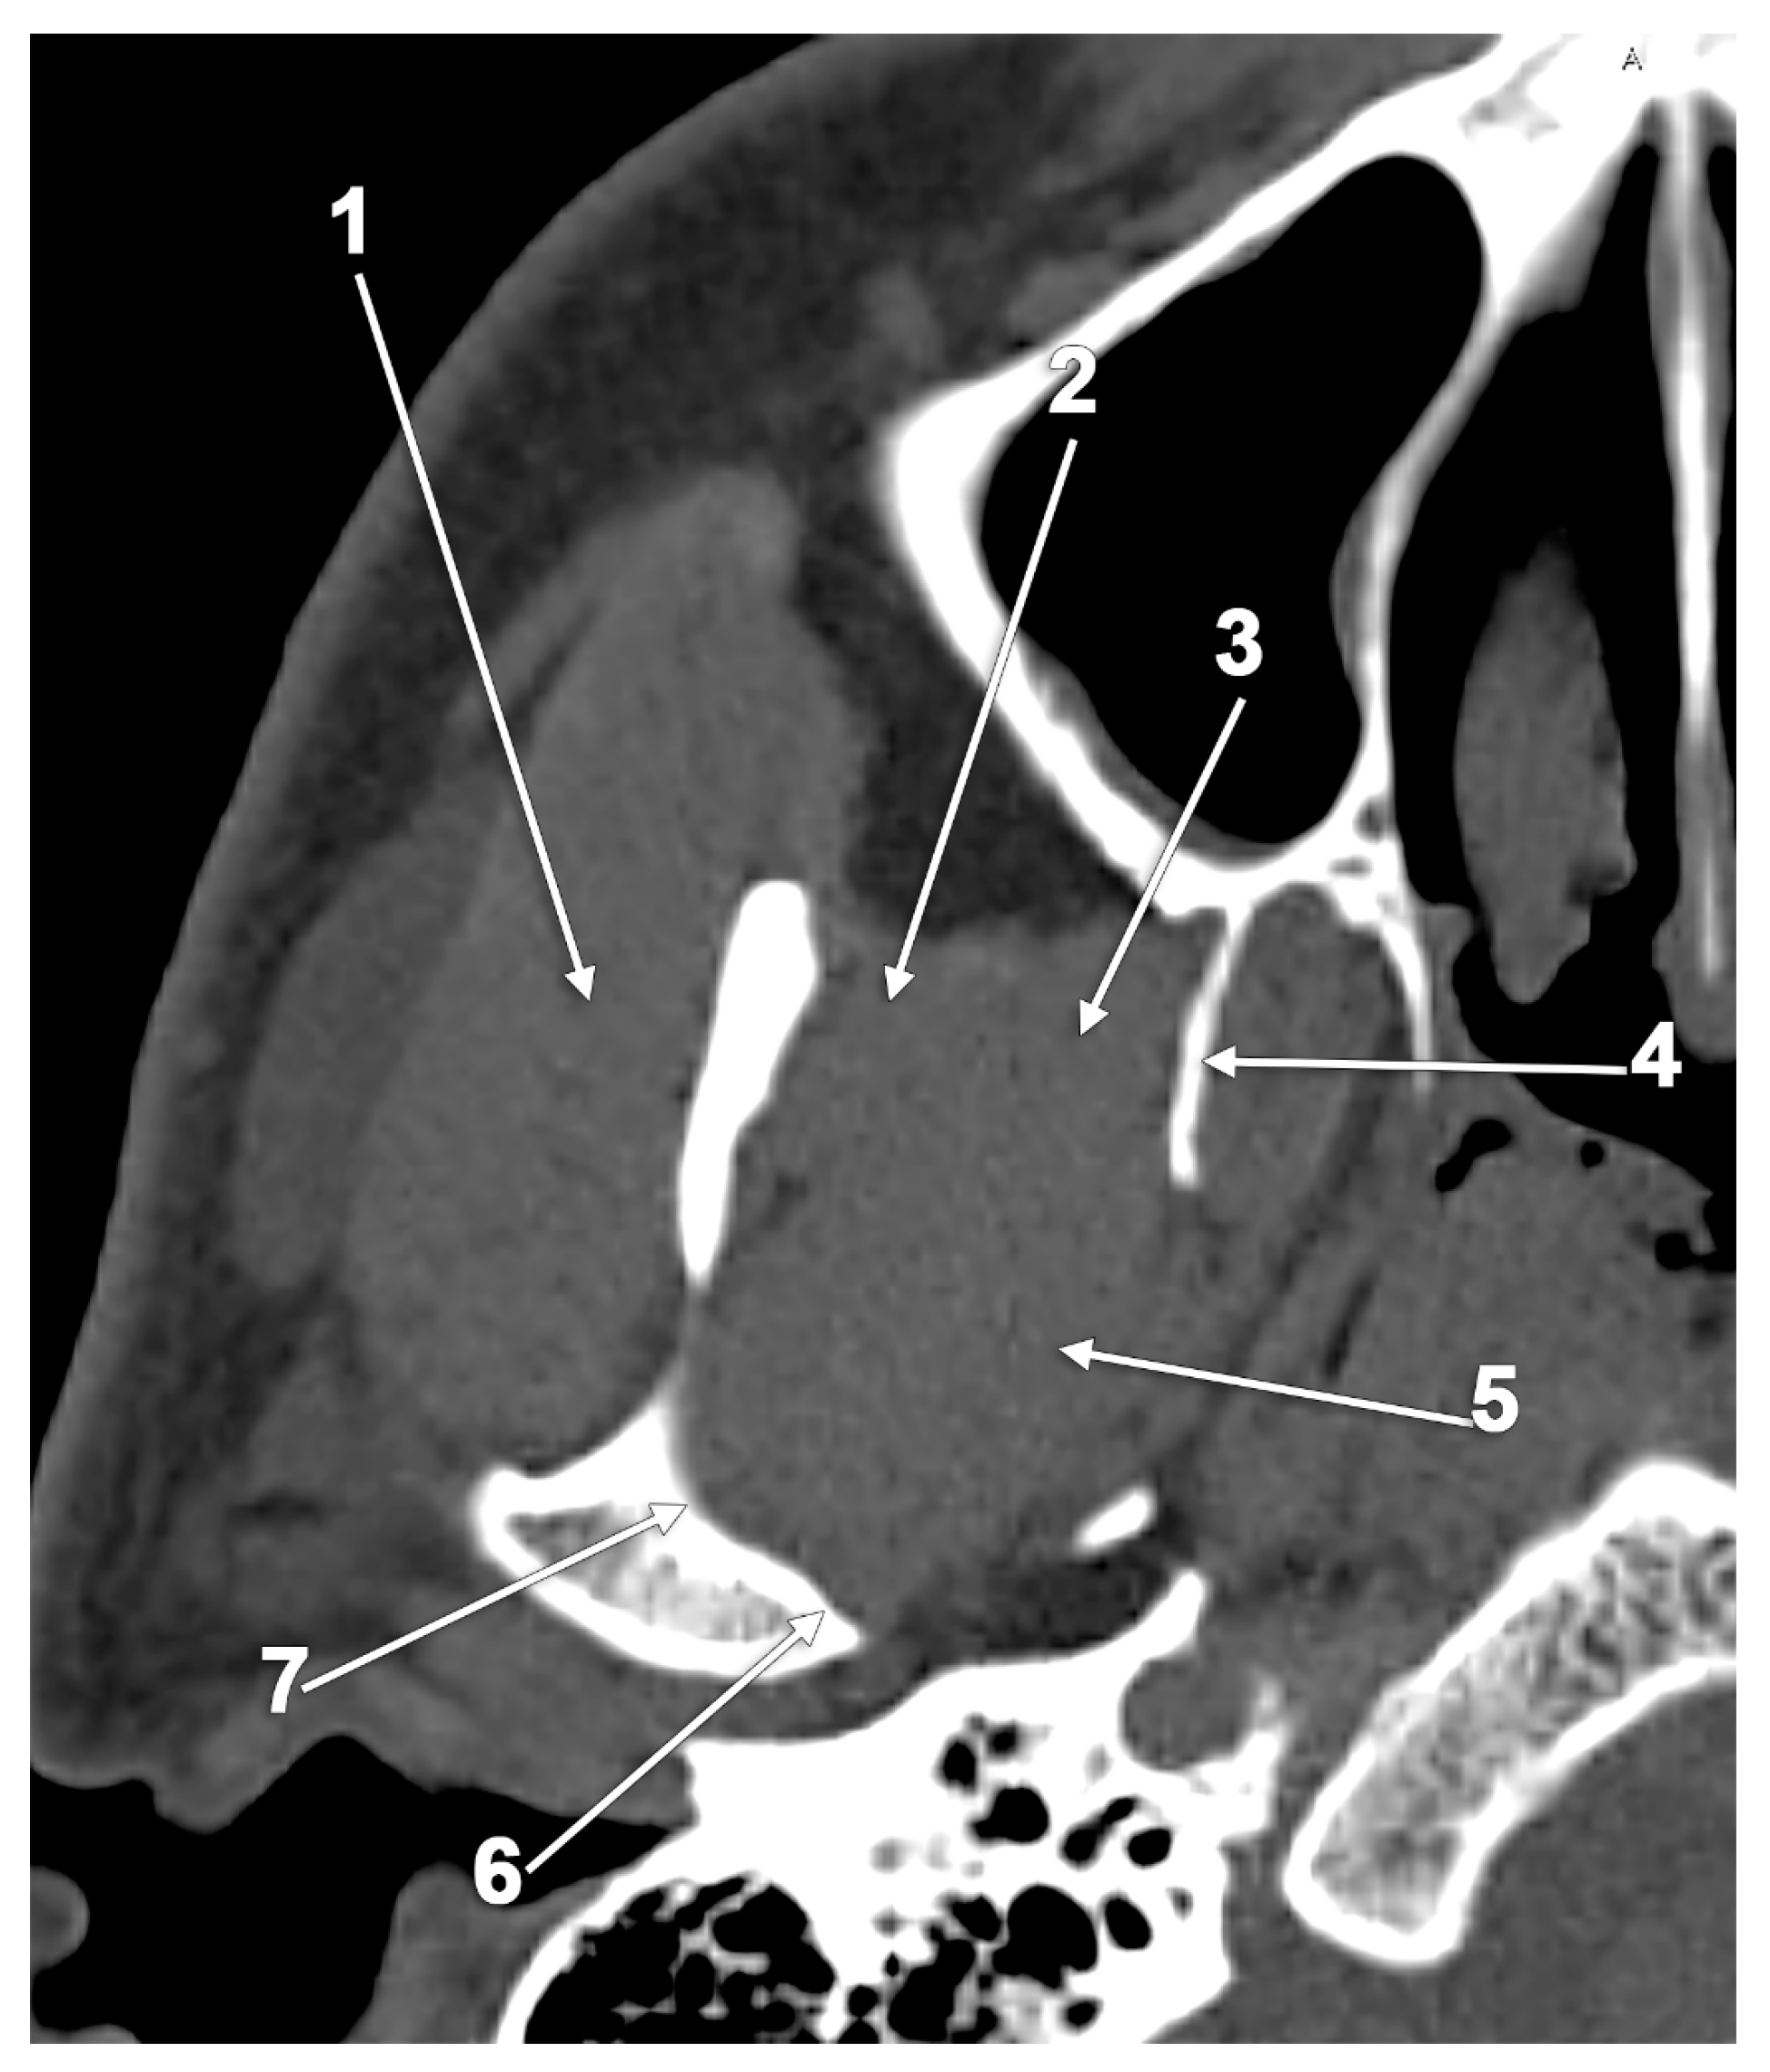

- Rusu, M.C.; Dinca, D. Accessory pterygoid fovea of the human mandibular condyle. Cranio 2021, 39, 452–456. [Google Scholar] [CrossRef] [PubMed]